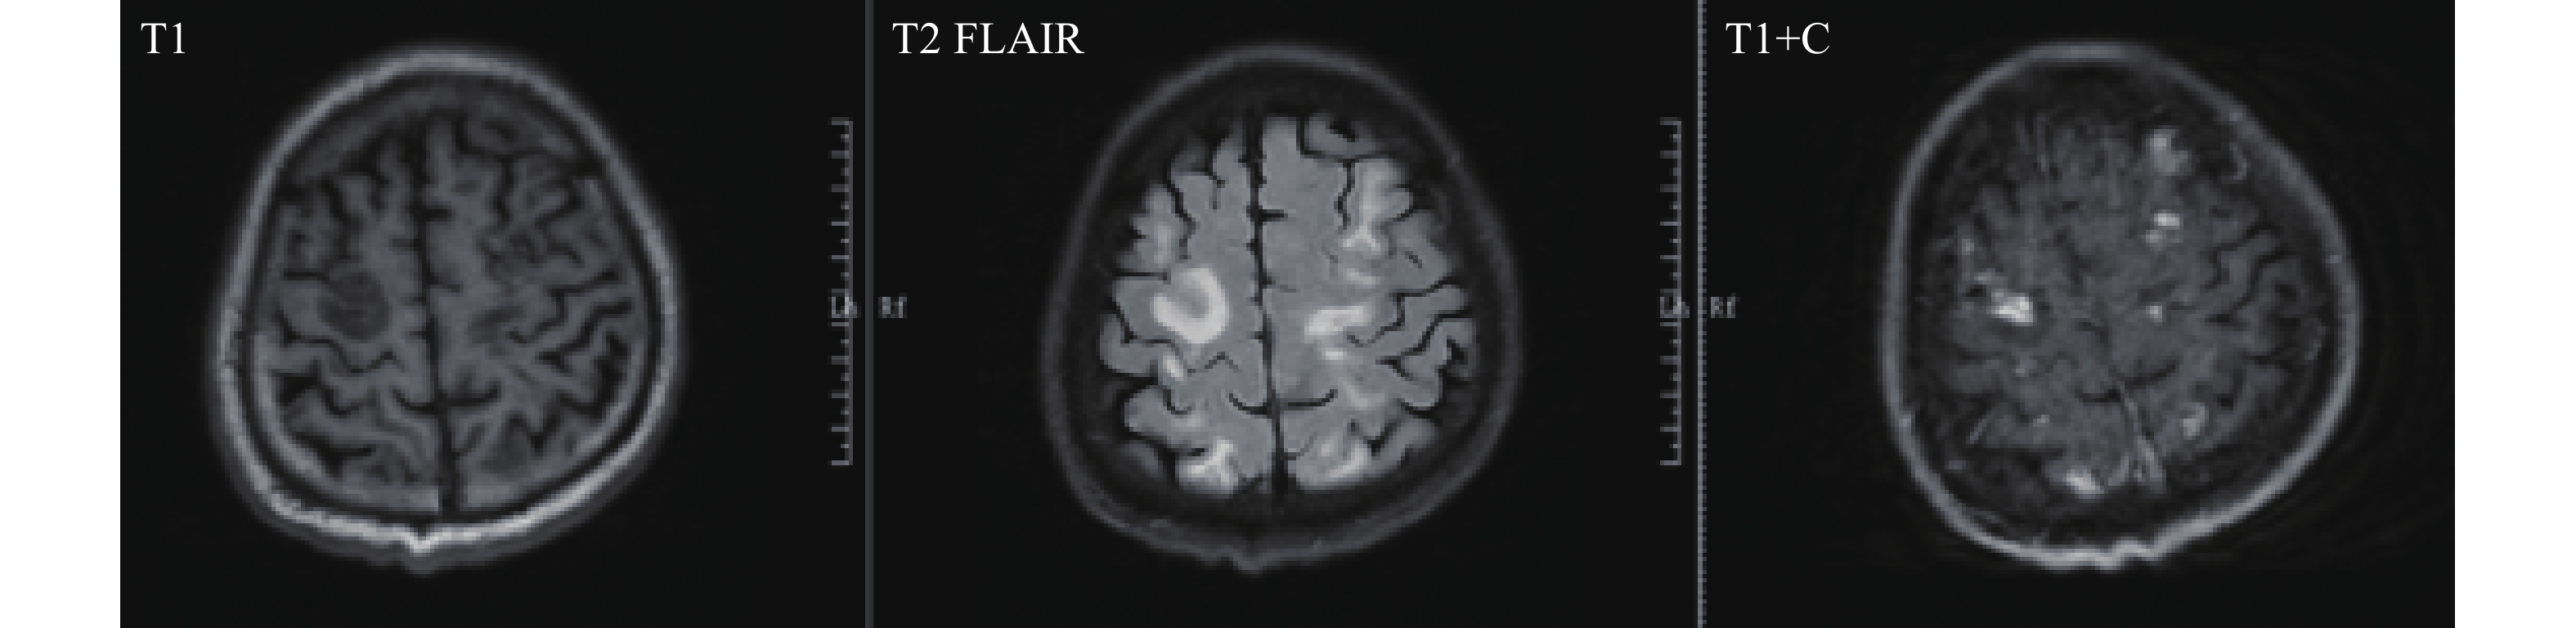

First Imported Case of Cerebral Schistosomiasis Mansoni — China, May 2025

Weiqi Chen, Yalan Zhang, Xiaohui Ma, Tiantian Jiang, Dongyang Zhao, Yan Deng

2026, 8(5): 131-134. doi: 10.46234/ccdcw2026.021

Schistosoma mansoni (S. mansoni) is predominantly distributed across Africa, the Middle East, the Caribbean Islands, and South America, infecting approximately 54 million people annually. China is not an endemic region for schistosomiasis mansoni, and no cases of cerebral schistosomiasis mansoni have been previously documented.

What is added by this report?

This report documents the first imported case of cerebral schistosomiasis mansoni in China. We present the epidemiological investigation, distinctive clinical manifestations, diagnostic challenges including misdiagnosis and delayed diagnosis, and the critical role of pathogen detection in case confirmation.

What are the implications for public health practice?

With the continuous emergence of imported S. mansoni cases and the gradual expansion of intermediate host breeding grounds, active monitoring should be conducted for potential risks of local transmission within China. To prevent this disease from becoming endemic, CDCs and medical institutions must strengthen their diagnostic, treatment, and prevention capabilities, as well as their monitoring and early warning capacities for imported schistosomiasis mansoni.